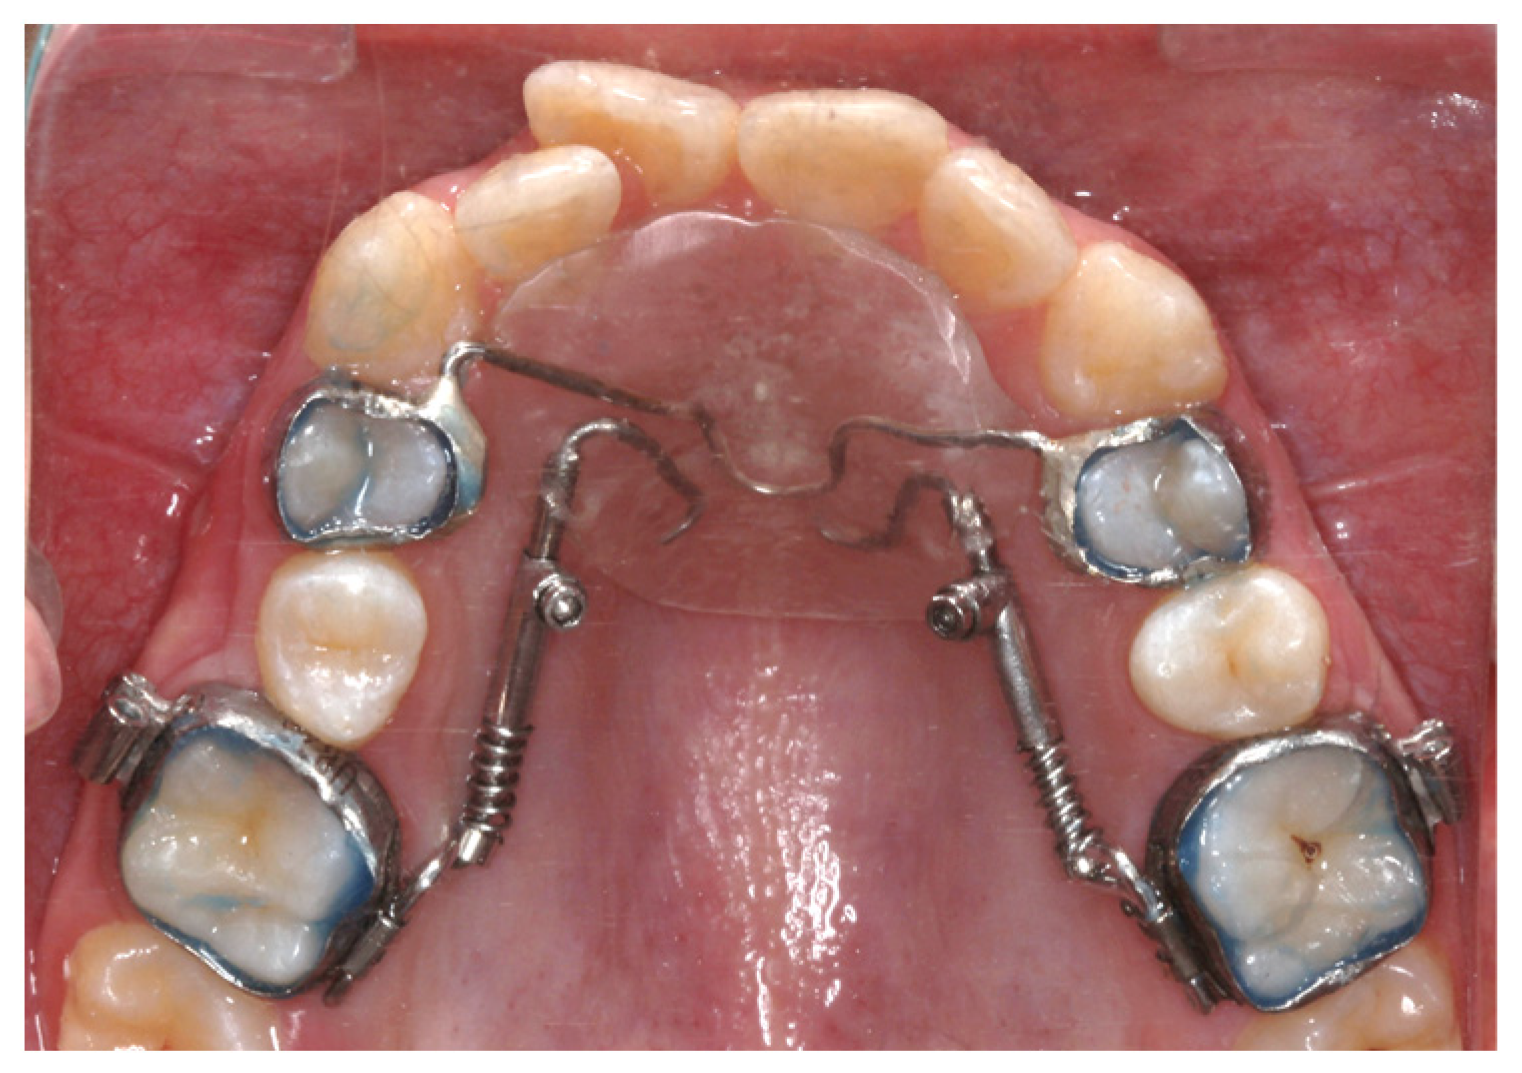

Beneslider Appliance

Modified Lokar Appliance

Miniscrew-Assisted Frog Appliance

Modified Distal Jet Appliance

Modified Pendulum Appliance